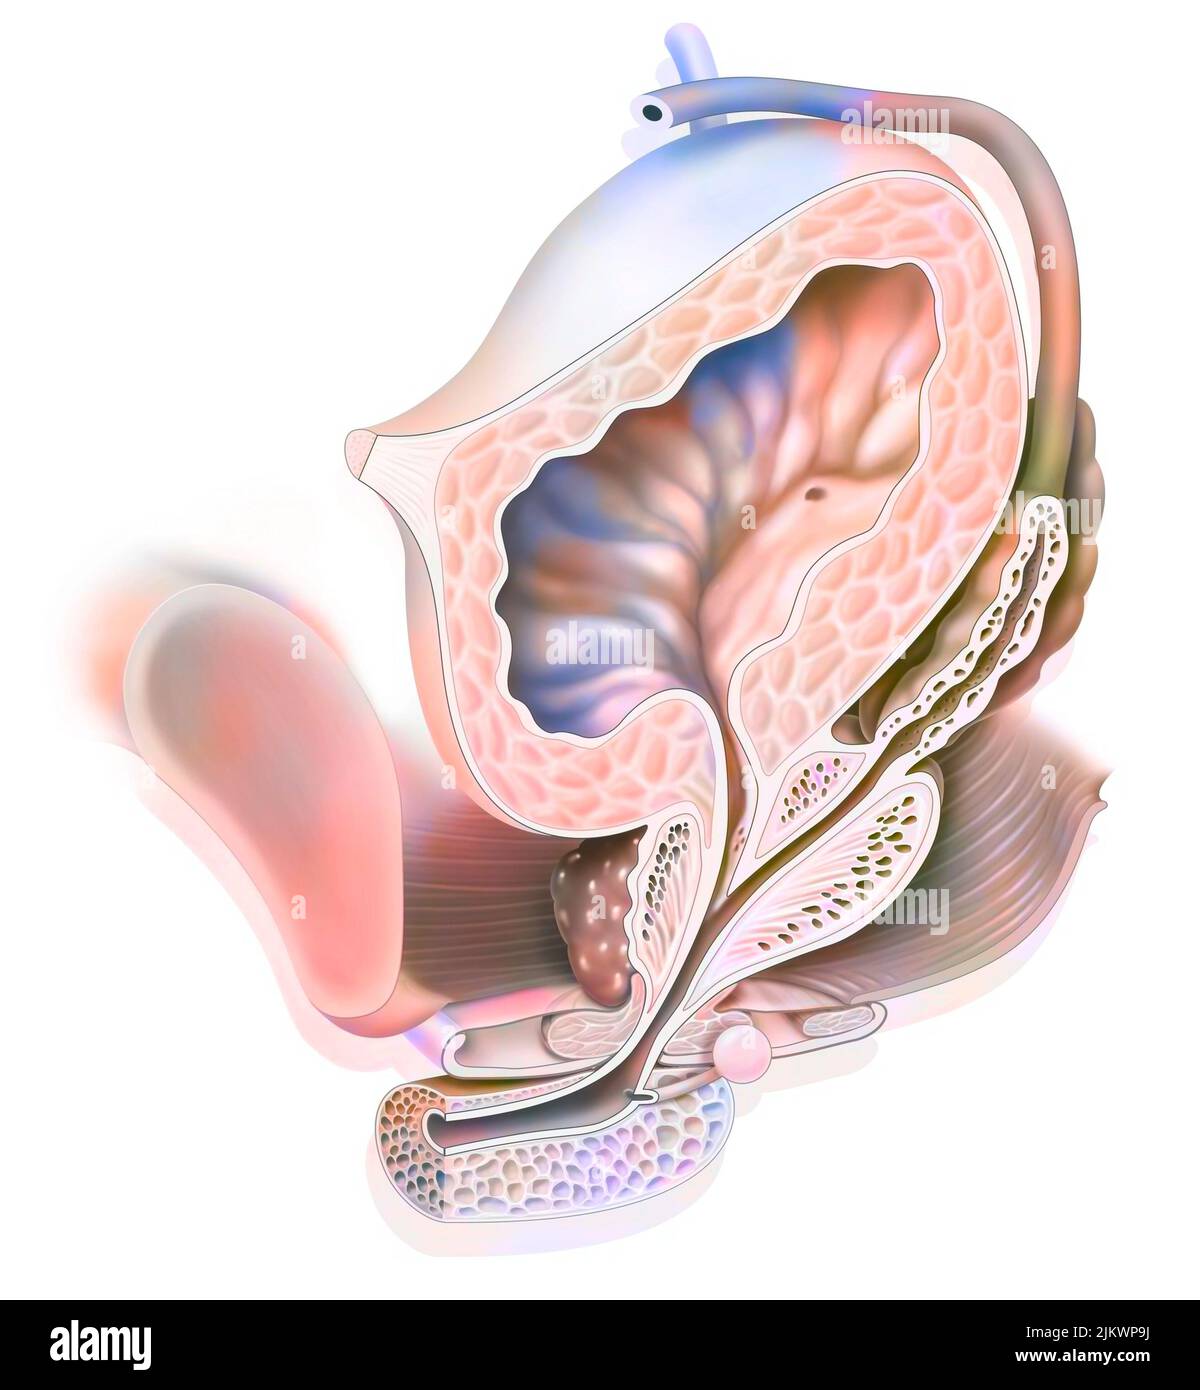

(4,132)Page 1 sur 42

Résultats de la recherche pour les photos et les images (4,132)

Page 1 sur 42